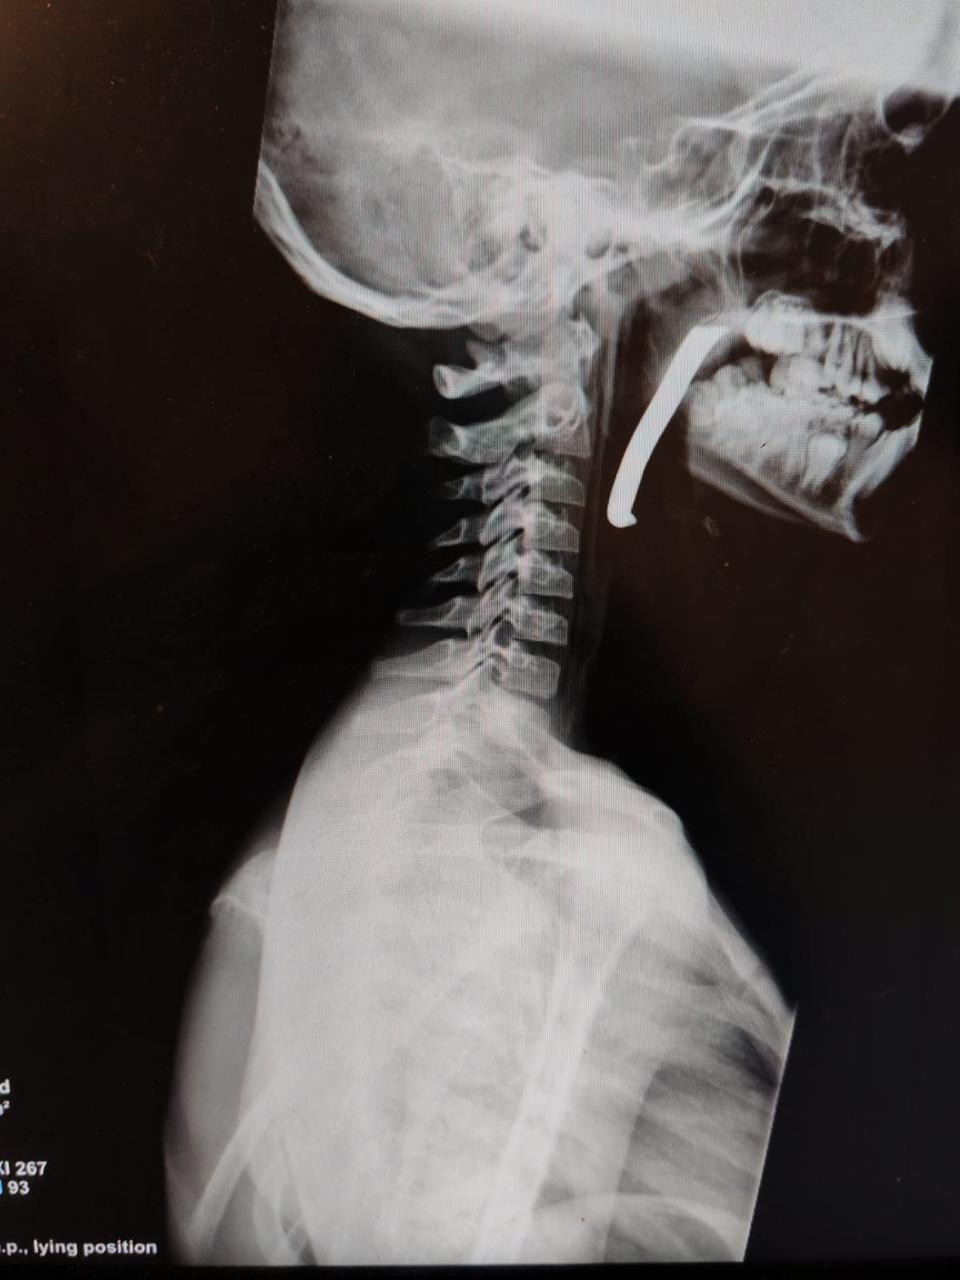

حصادنيوز – أجرت طواقم المستشفى الميداني الأردني جنوب غزة/6، أمس الأحد، عملية جراحية ناجحة لإنقاذ حياة طفل، تم خلالها استخراج شظية كبيرة الحجم اخترقت الرقبة والبلعوم والمجرى التنفسي، وذلك من خلال استكشاف جراحي دقيق للرقبة.

وأوضح مدير المستشفى أن الطفل كان يعاني من إصابة بالغة على مستوى الرقبة والبلعوم، حيث اخترقت الشظية مناطق حيوية وأدت إلى صعوبة في التنفس، مما شكل تهديداً مباشراً لحياته. وأضاف أن الحالة كانت حرجة، وتطلبت تدخلاً جراحياً فورياً نفذه فريق طبي متخصص يضم أطباء في الجراحة العامة، والتخدير والإنعاش، وجراحة الأطفال، وجراحة الأنف والأذن والحنجرة، وبمتابعة دقيقة من الأطباء المختصين، وتم استخراج الشظية بنجاح عن طريق الفم، وحالة الطفل الآن مستقرة.